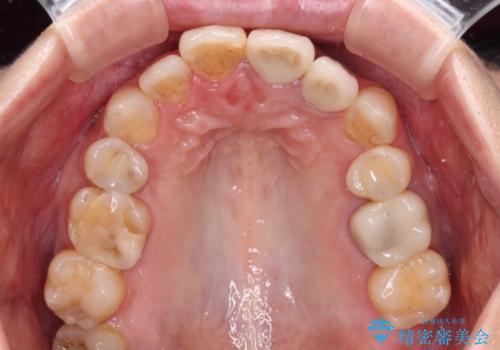

真ん中のオールセラミッククラウンを正面から見ると大変自然に仕上がっているのですが、側方から見ると白色が強く、さらには隣の歯は神経が除去されて変色していたため、コントラストでより色の違いが際立っていました。

前歯2本をオールセラミッククラウンにて補綴治療することとしました。